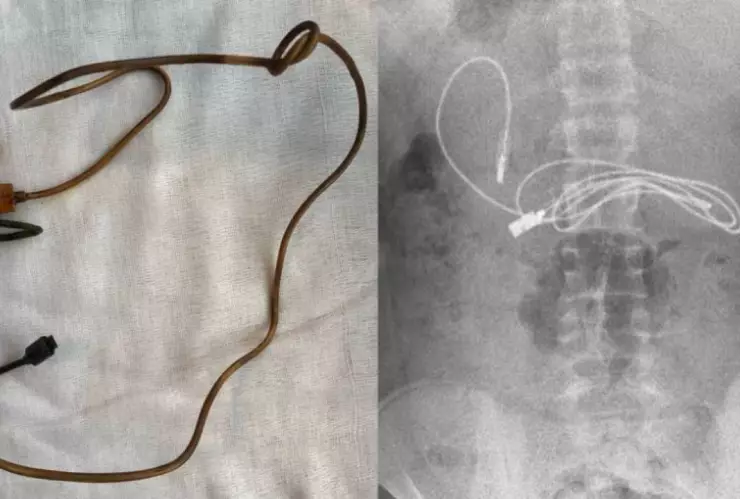

El gastroenterólogo pediátrico que atendió al menor, publicó una serie de fotografías de cómo se veía el cable atorado en su colon y cómo se vio una vez que lo retiraron de su cuerpo.

Afortunadamente, lograron retirar ambos objetos del cuerpo del menor, pero los doctores aseguraron que tuvieron bastantes dificultades, pues un extremo del cable había pasado al intestino delgado.